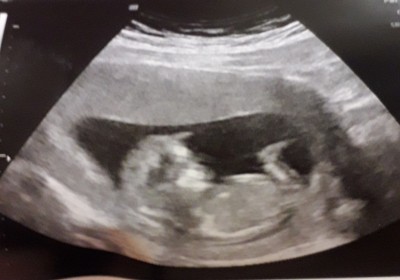

7 Ocak 2021 Hamilelik Dönemi Genel kategorisinde (32 puan) sordu

Tahminde bulunabilirmisiniz

Kapatılma nedeni: Cinsiyet tahminlerini sol üst köşeden konu dışı sohbetten sorabilirsiniz

Bizim görüntümüz aynısı 12+2 günlüğüm 2'li testim vardı doktor çok erken cinsiyet için dedi ❤️ Rabbim hakkında hayırlısini versin insallah